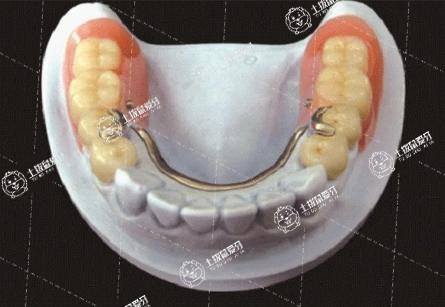

全瓷牙是可以取下來的,但是全瓷牙一取下來就不能再用了。烤瓷牙可以拆下來,但是拆掉后就不能再使用了,拆掉后的牙齒由于磨掉了很多的牙齒組織,必須再做烤瓷牙或者塑料牙修補起來,否則牙齒沒有咀嚼功能。烤瓷牙是恢復牙齒缺損及達到功能和美觀要求的修復牙冠,常用的烤瓷牙修復多為金屬烤瓷牙,全稱烤瓷熔附金屬全冠,是種低熔烤瓷在真空條件下熔附在鑄造金屬基底冠上的復合結構的修復體,兼具金屬的強度和瓷的美觀,優(yōu)點是能恢復理想的牙體形態(tài)和功能,色澤美觀穩(wěn)定,表面光滑,耐磨性好,耐腐蝕性。建議可以做烤瓷牙修復,修復后要注意保護自己的牙齒,避免牙鹵發(fā)炎。